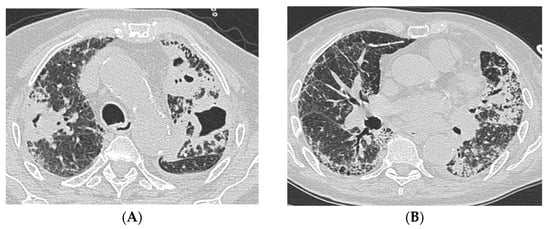

A 70-year-old male, former smoker, with known contact with active TB presented with productive cough and dyspnea on exertion. The patient was evaluated in an outpatient setting and underwent a chest X-ray, which showed reduced expansion of the left costophrenic sinus and accentuation of the lung pattern. A 10-day empiric course of antibiotics (prulifloxacin) and oral corticosteroids was prescribed; however, this treatment did not lead to any clinical improvement. The patient subsequently presented to the emergency department, where an initial evaluation revealed no respiratory failure but significantly reduced oxygenation levels relative to age. Laboratory tests showed an increased white blood cell count, moderately elevated inflammatory markers, mild anemia, and high ferritin levels. A subsequent chest CT scan revealed no parenchymal consolidations but demonstrated diffuse reticular thickening of the intra- and interlobular septa, more pronounced in the subpleural regions and the posterior segments of the lower lung lobes. Additionally, honeycombing and multiple traction bronchiectasis were observed. Given the persistence of symptoms and a productive cough unresponsive to first-line therapy, an induced sputum sample was obtained. PCR for Mycobacterium tuberculosis on the sample was positive.

Antitubercular therapy with rifampin, isoniazid, ethambutol, and pyrazinamide was initiated during hospitalization, with good tolerability and no evidence of hepatic toxicity. After two weeks of treatment, the patient was discharged home. Upon reevaluation in the outpatient clinic the following week for a suspected allergic reaction, pyrazinamide was discontinued and replaced with moxifloxacin. Concomitantly, the case underwent MDD, where the diagnosis of IPF was made. Upon completion of antitubercular treatment for 6 months, antifibrotic therapy with nintedanib 150 mg was initiated, with good tolerability.